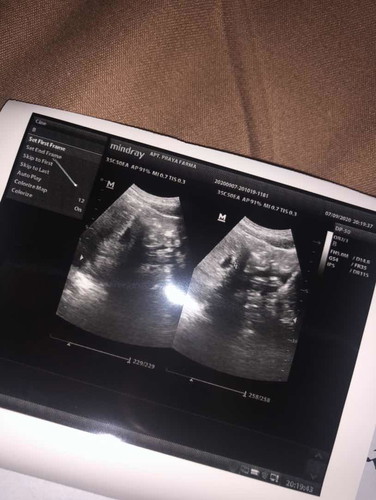

aku hamil kata dokter 4 minggu nah sekarang gejalanya seperti orang masuk angin bingung mau minum obat apa🙁